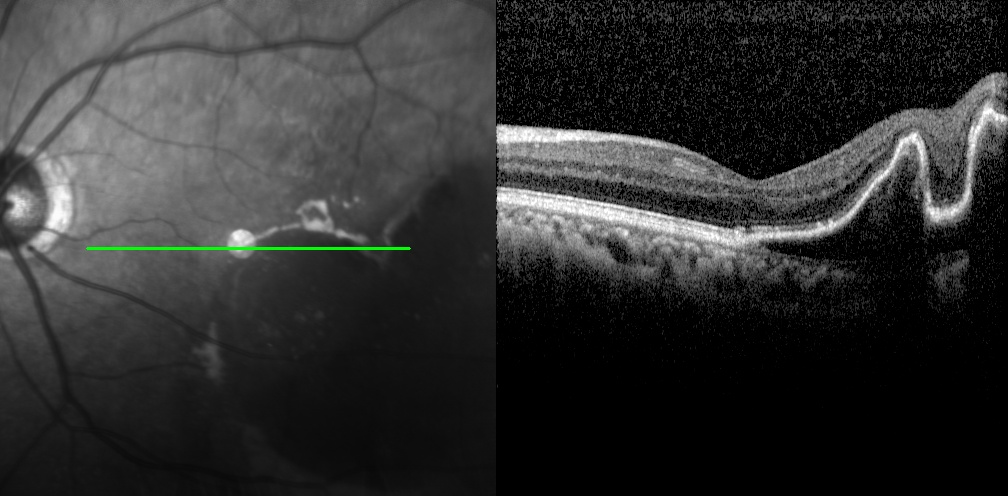

老王左眼检查图片

左眼调整用药半个月后检查图片